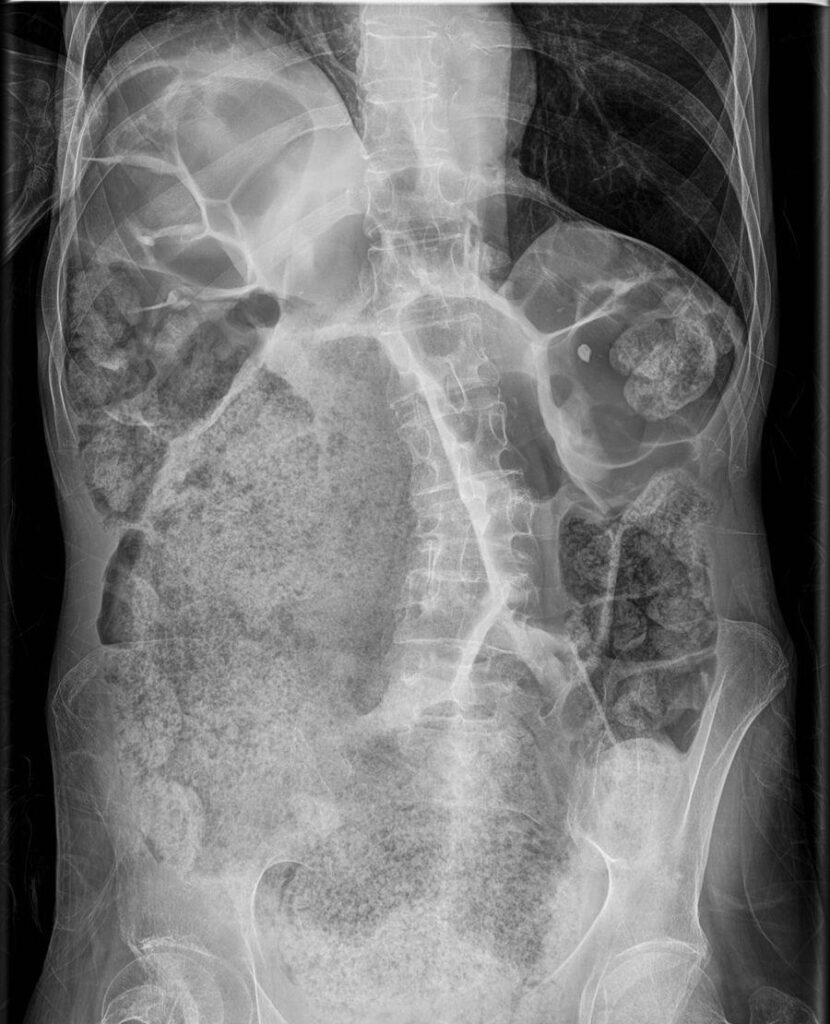

Sin embargo, en casos de coproestasis, este proceso se ve alterado. La acumulación de heces endurecidas en el colon dificulta su paso a través del sistema digestivo y su evacuación. Esto puede ser causado por varios factores, como la falta de movilidad intestinal, la deshidratación, una dieta pobre en fibra o trastornos neuromusculares, entre otros. La acumulación de heces endurecidas en el colon puede provocar síntomas incómodos, como distensión abdominal, dolor, malestar y, en casos graves, obstrucción intestinal.

Los síntomas comunes de la coproestasis pueden incluir:

- Distensión abdominal.